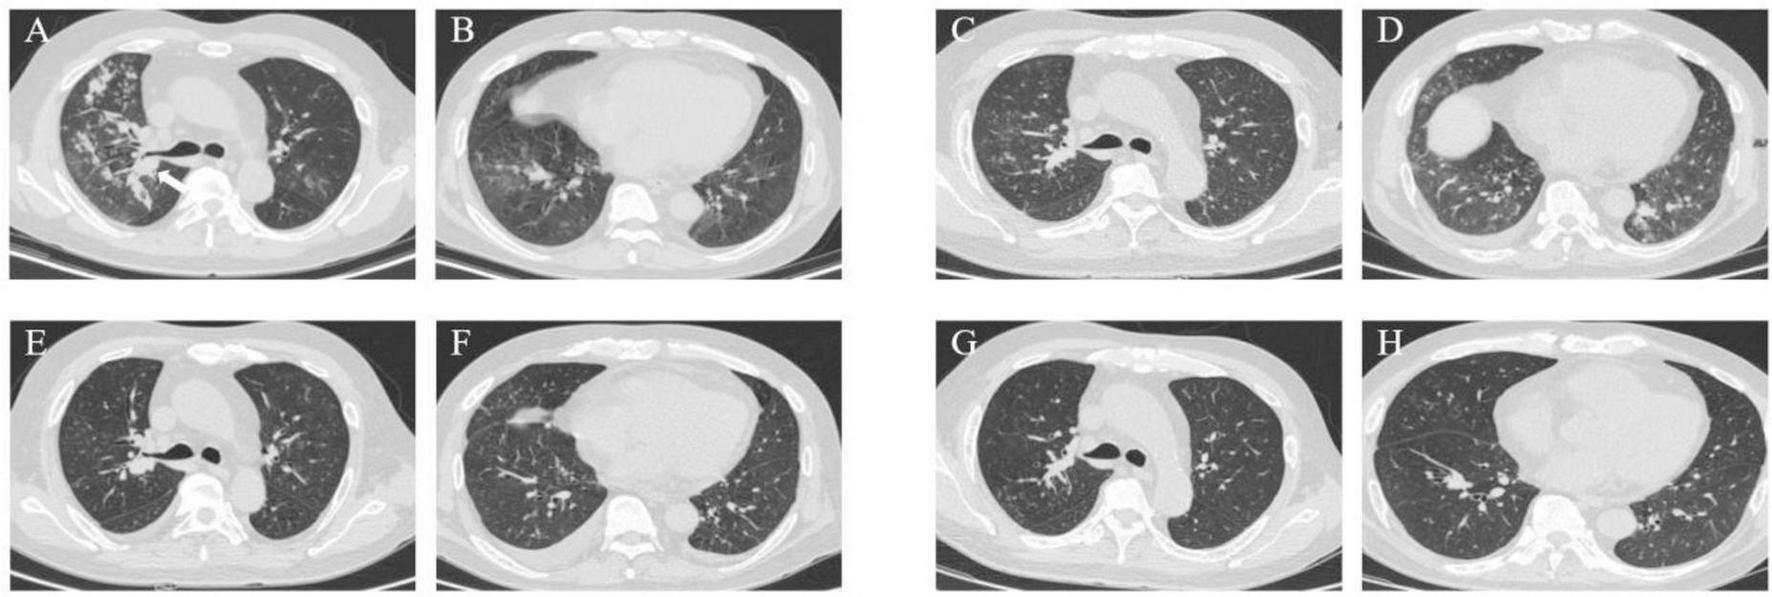

A 73-year-old male was hospitalized on 30 March 2023, with a two-month history of a productive cough and shortness of breath, which had worsened over the past week. A previous chest CT scan from another hospital revealed bronchiectasis and a suspected infection in the upper lobe of the right lung. The patient had experienced a weight loss of 5 Kg in the preceding week. Upon admission, a chest CT scan revealed multiple ill-defined pulmonary nodules in both lungs, with the largest area of consolidation (measuring 3.5 cm × 4.4 cm) located in the left lower lobe, characterized by inhomogeneous density (arrow) (Figures 1A, B).

FIGURE 1

Case 1, Chest CT scans. (A, B) On March 30: multiple ill-defined pulmonary nodules in both lungs. The largest areas of consolidation appearing with inhomogeneous density. In the left lower lobe, diagonal measurement result was 3.5 × 4.4 cm (arrow). (C, D) On April 7: patchy opacities and ground-glass attenuation in both lungs. (E, F) On April 14: partial resolution of the inflammation. The largest consolidated nodules enlarged to 4.8 × 6.2 cm (arrow). (G, H) On April 27: multiple patchy opacities of the left lung were further absorbed than that on April 14, while opacities of the right lung were similar to before. (I, J) On June 26: the pulmonary nodules and patchy opacities were gradually resolving after systemic therapy. The largest consolidation was about 4.0 × 3.3 cm (arrow). (K, L) On August 30: the pulmonary nodules and patchy opacities gradually diminished.

On March 30, the patient continued with 24 mg of MP daily (Figure 2). Starting March 31, sulfamethoxazole-trimethoprim (SMX-TMP) injections were administered every 8 h to target Nocardia and PJ. After six days, due to adequate blood drug levels, the regimen was adjusted to 160 mg every six hours. Meropenem (1 g every 12 h) and ganciclovir (125 mg every 12 h) were prescribed for antibacterial and antiviral purposes, respectively. By April 4, inflammatory markers (CRP: 33.8 mg/L; PCT: 1.26 ng/mL) had decreased, reflecting slight clinical improvement. However, a chest CT on April 7 revealed progression of pneumonia (Figures 1C, D). Despite this, the treatment plan was maintained due to the delayed response in imaging. MP remained the sole immunosuppressive drug.

By April 13, there was a significant improvement in the patient’s symptoms, evidenced by the reduction in cough, sputum production, and wheezing. Arterial blood gas analysis showed normalization [FiO2: 43%, pH: 7.54, PO2: 125 mmHg, PCO2: 27 mmHg, : 26 mmol/L, SaO2: 99.4%, oxygenation index (OI): 291 mmHg], and inflammatory markers (CRP: 22.4 mg/L; PCT: 0.40 ng/mL) continued to decline. CMV DNA tests were negative twice consecutively. On April 14, partial resolution of pulmonary inflammation was observed via CT, although the largest consolidated nodule had increased to 4.8 cm × 6.2 cm (arrow) (Figures 1E, F). Meropenem and ganciclovir were discontinued.

VOR (April 1–April 13) was initially used for antifungal treatment but was replaced by ISA on April 14, due to suboptimal blood levels resulting from rapid drug metabolism. ISA was administered as 200 mg every 8 h for the first 48 h, followed by 200 mg daily. Additional treatments included SMX-TMP (21 days), rifampin (0.45 g qd), clarithromycin (500 mg bid), and ethambutol hydrochloride (0.75 g qd) for NTM. On April 17, the BALF fungal culture revealed no growth. By April 27, the left lung opacities showed further resolution, while the right lung opacities remained stable (Figures 1G, H).

Despite financial constraints leading to ISA (April 14–May 29) discontinuation after 45 days, follow-up on June 26 showed further reduction in pulmonary lesions. The largest consolidation had decreased to 4.0 cm × 3.3 cm (arrow) (Figures 1I, J). By August 30, pulmonary nodules and patchy opacities had gradually diminished.